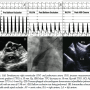

A 36-year-old woman had a 22 mm secundum atrial septal defect with concomitant infundibular pulmonic stenosis (Figure 2). Cardiac catheterization demonstrated Qp:Qs of 2.8:1 with a mean transpulmonic gradient (TPG) of 35 mm Hg. TBO decreased TPG to 18 mm Hg due to reduction in flow across the right ventricular outflow tract. After deployment of a 24 mm Amplatzer cribriform atrial septal occluder, TPG was 14 mm Hg.

TBO can also be useful in the evaluation of suitability for closure of an ASD in patients with congenital lesions. Patients with hypoplastic right heart may be intolerant to ASD closure due to inability to accommodate systemic venous return.9,10 Pulmonic stenosis also presents a diagnostic dilemma due to underestimation of the valvular area due to increased flow from the interatrial shunt. The question as to whether or not the valve lesion is severe enough to warrant surgical correction cannot formally be assessed until after ASD occlusion.2 The second case highlights the importance of further evaluation of ASD closure in patients with concomitant pulmonary stenosis. The increased flow throughout the pulmonary valve due to an ASD may overestimate the valvular gradient. TBO allows adequate assessment of the resultant gradient to determine if any additional intervention to the pulmonary valve is indicated. In our case, the patient had an infundibular stenosis, which would have prompted a surgical correction had the gradient remained significantly elevated following TBO.